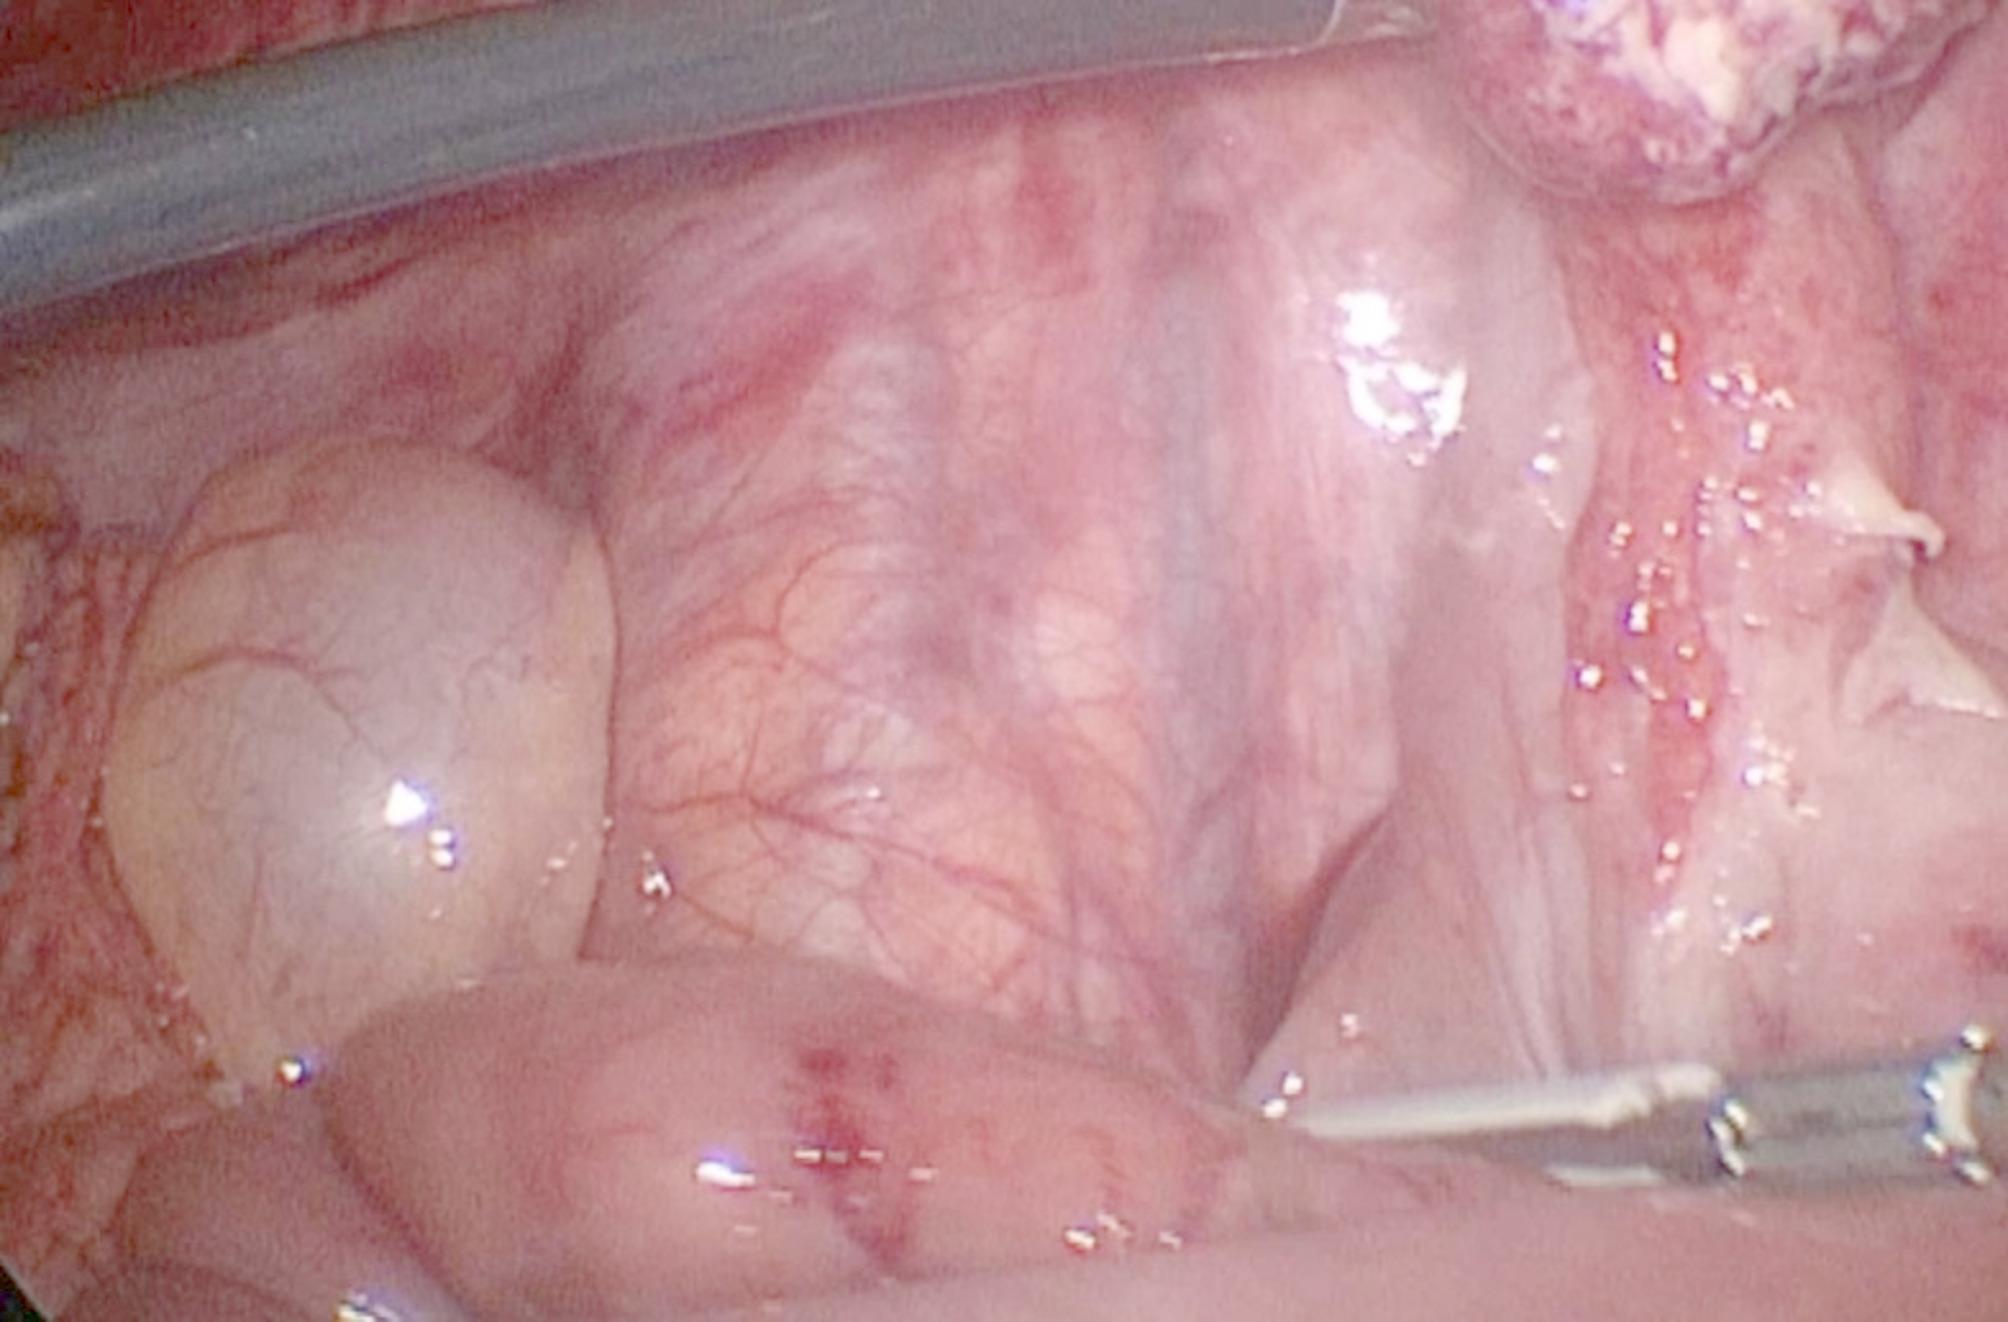

Case presentation: An 11-year-old boy presented with persistent suprapubic pain and dysuria for one week. Initial urine analysis revealed turbid urine with high numbers of red blood cells, leading to a diagnosis of urinary tract infection (UTI), and antibiotic treatment was initiated. However, the patient's symptoms persisted, with worsening clinical signs. A complete blood count revealed leukocytosis with neutrophilia, suggesting the need for further evaluation. A non contrast computed tomography (CT) scan revealed a thickened, blind-ended structure in the midline lower abdomen with gas, extensive fat stranding, and associated mesenteric lymphadenopathy, suggestive of perforated Meckel's diverticulum. The patient underwent laparoscopic exploration, which revealed an abscess caused by perforated Meckel's diverticulum adherent to the urinary bladder. Diverticulectomy and incidental appendectomy were performed via a stapling device. Pathology confirmed a perforation of Meckel's diverticulum with serofibrinous peritonitis and follicular appendicitis. The postoperative course was uneventful, with the patient resuming full oral intake by the fifth day and being discharged in stable condition.